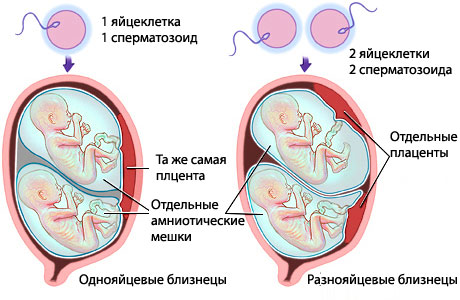

Багатоплідної зачаття буває однояйцевих і двуяйцевие. У першому випадку вагітність виникає в результаті поділу однієї заплідненої яйцеклітини.

В результаті утворюються два плоди однієї статі і з схожим генетичним хромосомним набором, ще їх називають близнюками.

Двуяйцевие вагітність є результатом поєднання процесу овуляції і статевого акту: з фолікулів виходить одночасно дві дозрілих яйцеклітини, які згодом запліднюються.

В даному випадку народилася двійня матиме тільки 50% однакових генетичних рис і абсолютно різний хромосомний набір.Вирушаючи на УЗД, батьки поспішають поцікавитися, хто у них з'явиться, хлопчик чи дівчинка.